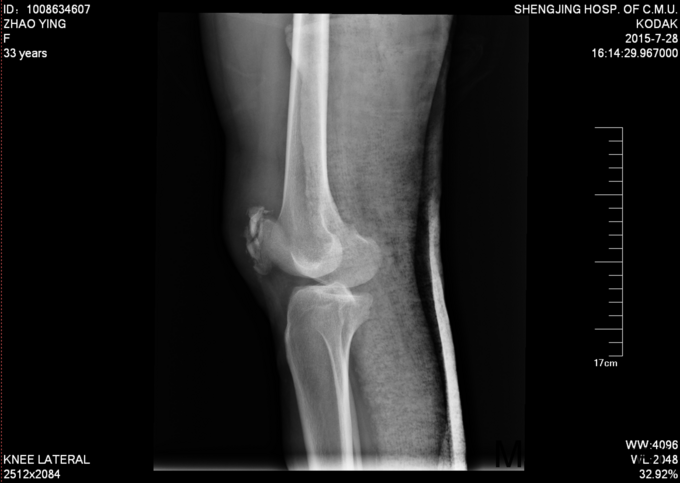

现病史:患者家属代诉于2015年7月23日5点发生车祸,车祸后致右膝部疼痛肿胀活动受限,当时无意识不清,120送至当地医院(辽中县医院),后为进一步治疗,急诊就诊于中国医科大学附属盛京医院,行X线片检查示:右髌骨开放性骨折,急诊给予清创缝合,观察患者病情稳定后,急诊以“右髌骨开放性骨折”为诊断收住我科·。伤来患者无头痛及发热,无咳嗽咳痰,无腹痛及恶心呕吐,饮食睡眠可,大小便正常。

专科查体:患者轮椅入病房,右膝部不规则缝合术后,右膝部肿胀明显,疼痛,压痛(+),活动受限,骨擦音,骨擦感(+), 患肢足趾活动可,足背动脉可触及。

入院后完善检查,患者创口换药,观察患者创口变化,于一周后无红肿渗出后,无发烧发热后。查无手术禁忌症后行右髌骨骨折切开复位张力带内固定术